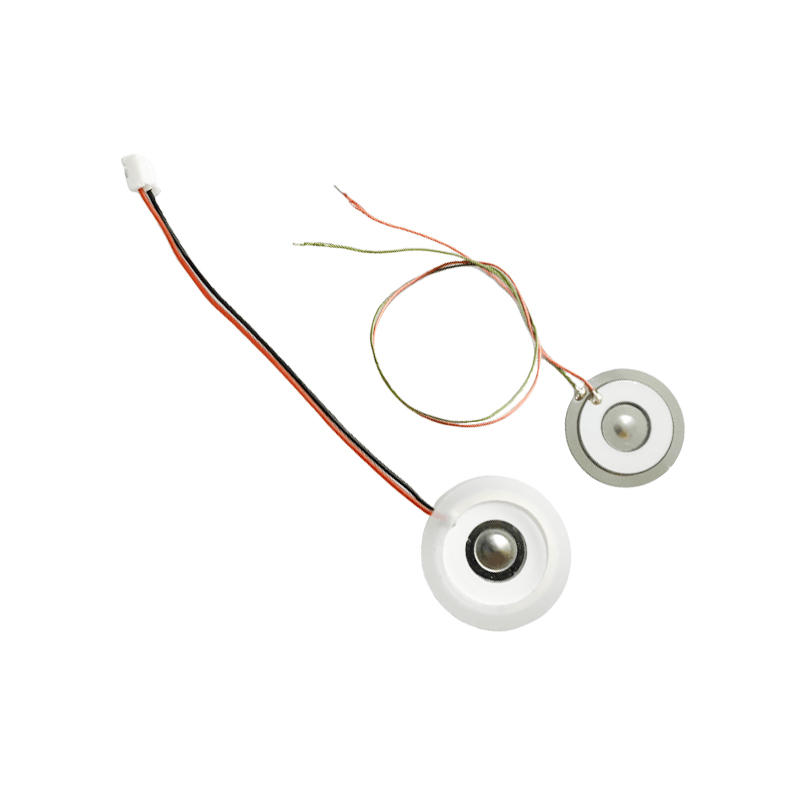

Polyimid (Polyimid) označovaný jako PI, je nejlepší komplexní výkon organických polymerních materiálů, má vynikající chemickou stabilitu a může odolat korozi různých léků, aby bylo zajištěno dlouhodobé používání atomizovaných tablet. Kromě toho je vynikající tepelná stabilita polymerního PI filmu, s dlouhodobým používáním teplotního rozsahu -200 ~ 300 ° C, vysokou izolací, ochranou životního prostředí a netoxicitou, jako speciální inženýrský materiál, široce používaný v letecké mikroelektronice, separační membrány z nano-kapalných krystalů a další obory, byl v 21. století zahrnut zeměmi jednoho z nejslibnějších inženýrských materiálů. deformované v procesu vysokoteplotní dezinfekce, aby bylo zajištěno opětovné použití! Pro sex a bezpečnost používáme laserovou technologii pro laserovou perforaci, PI film implantovaný mezi nerezovou ocel a piezoelektrickou fólii, použití piezoelektrické keramické ultrazvukové technologie tak, aby se atomizované kapičky přes PI film rozptýlily do atomizace 3 ~ 4 μm částic pro inhalaci lékařskou nebulizací, bezpečnost většiny uživatelů miluje, vyrobeno z hlavního nebulizéru s PI výhoda non-ucpání, vnitřní stěna otvoru v hladké a zaoblené, žádné zbytky kapaliny, atomizace jemné a stabilní. Atomizace je jemná a stabilní. Tablety PI filmového nebulizátoru mohou účinně zabránit zbytkům léků, snížit riziko křížové kontaminace. V praktické aplikaci se také promítly charakteristiky nízké spotřeby energie polymerních PI membránových nebulizačních tablet, shrnuto, polymerové PI membránové nebulizační tablety se se svým vynikajícím výkonem a konstrukčními výhodami staly nepostradatelnou součástí oblasti lékařské nebulizační terapie.

Ultrazvukový atomizér je zařízení, které využívá principu ultrazvukové vibrace (přeměny energie) k přeměně kapaliny na drobné kapičky. Pracovní princip spočívá v jedinečných piezoelektrických vlastnostech piezoelektrické keramiky, atomizační kus při příjmu odpovídající buzení signálu elektrického pole, bude produkovat odpovídající oscilační frekvenci, prostřednictvím role vysokofrekvenční vibrace kapalné kavitace odhozené z povrchu vody, aby se vytvořil druh částic vodní mlhy, atomizovaný velkým počtem záporných iontů a malých částic molekul, dosáhnout zvýšení okolní vlhkosti, role čerstvého vzduchu. Povrch atomizéru je potažen skelným smaltem při vysoké teplotě 800 stupňů pro ochranu stříbrných elektrod piezoelektrického plechu, zvýšení odolnosti atomizéru vůči kyselinám a zásadám a oxidaci a zvýšení životnosti atomizéru. Široce se používá ve vnitřních zvlhčovačích, čističkách vzduchu, ošetření lékařských rozprašovačů a kosmetických automobilech, e a dalších oblastech, ale také vhodné pro sklady, továrny, zvlhčování, dezinfekci, k vytvoření atmosféry zvlhčovacího zařízení. Zamlžovací tablety se používají hlavně při průmyslovém zvlhčování, lékařském zamlžování, aromaterapeutickém zamlžování, zvlhčování prostředí, zamlžování zahrady a dalších scénách.